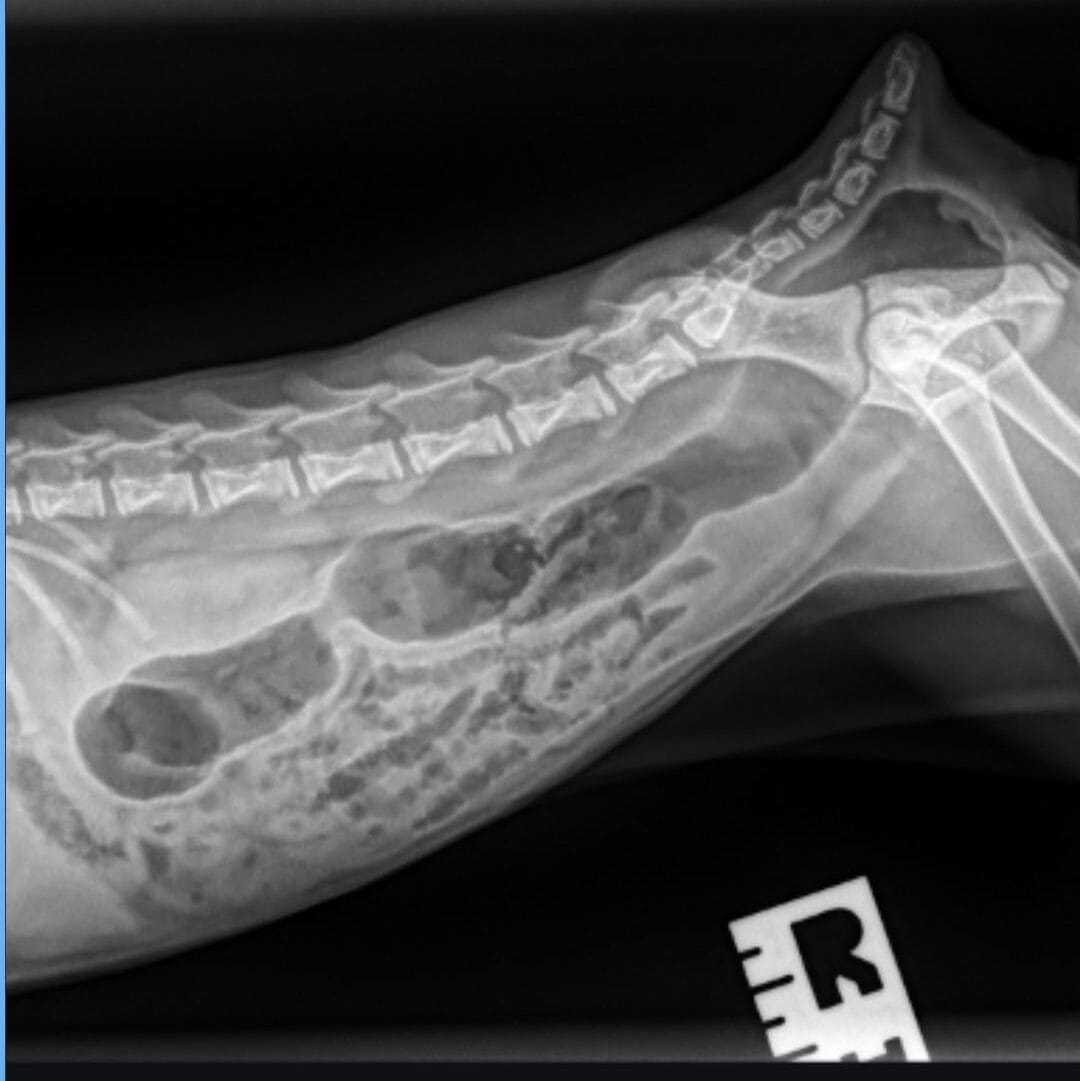

“When the vet brought back the X-rays, we all held our breath,” Tate said.

“There was a moment of dead silence and then we just lost it. Even the vet was laughing.”

The culprit behind all the drama? Gas.

Not a blockage. Not a swallowed Lego. Not anything sinister at all.

Just a spectacular case of trapped gas that had left poor Midas bloated, uncomfortable, and not his usual self.

“Gas. So. Much. Gas,” Tate wrote when she shared the story online. “He was just… full of farts. $900 worth of farts.”